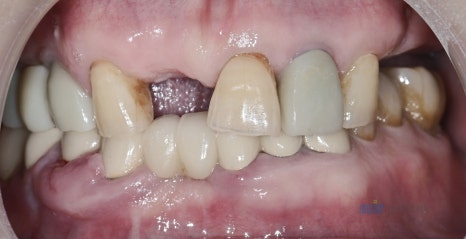

์์ ์ ํ๋ ธ๋ผ๋ง์ ๊ตฌ๊ฐ์ฌ์ง